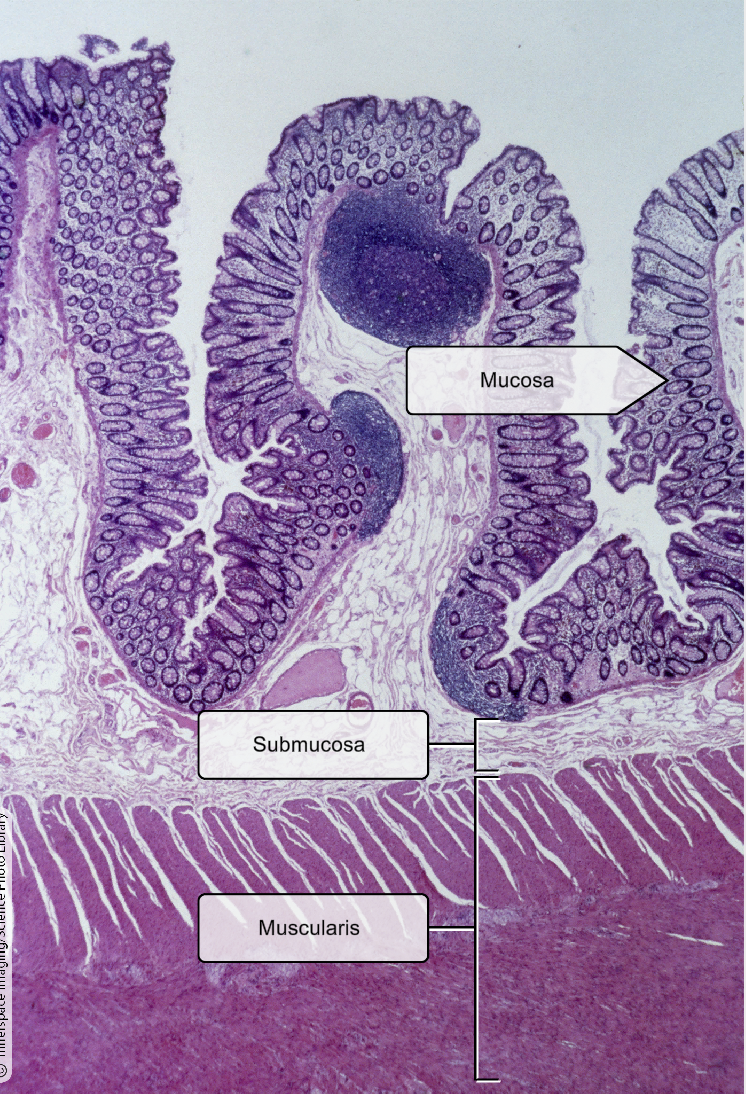

List the layers in the small intestine

Mucosa- ciliated pseudostratified columnar epithelium